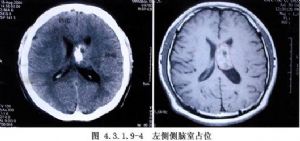

側腦室內腫瘤的發生率較低,據國內外文獻報道約佔顱內腫瘤總數的0.75%~2.8%。在側腦室前部和體部者,多爲室管膜瘤,在三角部、顳角和枕角區者,多爲乳頭狀瘤或腦膜瘤。側腦室周圍、丘腦和腦室室管膜下生長的膠質瘤,也可長入腦室內。其他如上皮樣囊腫或皮樣囊腫等也偶可見到。側腦室內腦膜瘤約佔顱內腦膜瘤的2.5%~6.3%,以女性較多,年齡多在30歲左右,且好發於左側側腦室。室管膜瘤則以嬰幼兒和學齡前兒童多見(圖4.3.1.9-1~4.3.1.9-6)。

頸動脈造影顯示脈絡膜前動脈增粗,椎動脈造影顯示脈絡膜後動脈增粗、走行異常和腫瘤染色等,都是確診側腦室腫瘤的有力依據。自CT、MRI問世以來,確診已較簡易、安全。由於手術經驗的積累,療效亦不斷提高,大多能全切治癒。